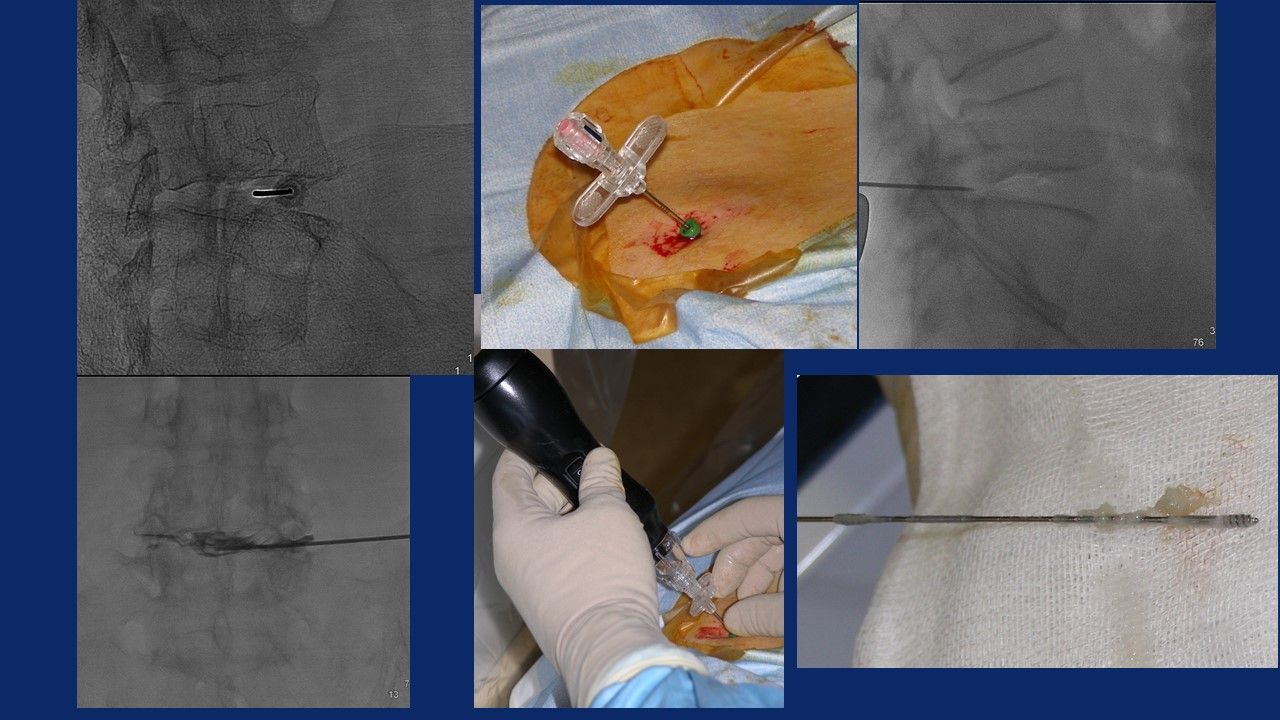

Ho maturato una notevole esperienza nella chirurgia mininvasiva percutanea del rachide, in particolar modo:

- nel trattamento della patologia discale mediante procedure di discectomia percutanea sotto guida fluoroscopica:

Nucleoplastica, Discectomia meccanica, Discectomia mediante laser, Discectomia Endoscopica, Discectomia mediante Discogel

Presento esperienza pluriennale nelle tecniche di biopsie Eco, TC e RM guidate per la caratterizzazione di lesioni a carico dell’apparato scheletrico, dei tessuti molli, degli organi addominali e del torace; e nei trattamenti ablativi con termoablazione, crioablazione e microonde, delle lesioni tumorali , in particolar modo ossee , renali e tiroidee.